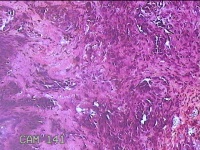

左侧耳廓结节

性别

男

年龄

11岁

临床诊断

皮下结节

一般病史

发现左侧耳廓结节10余年。

标本名称

大体所见

灰白暗红色带皮肤样结节0.8x0.3x0.2cm一个,表面糜烂。